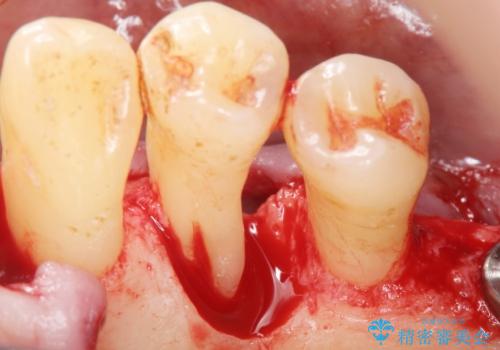

精査したところ、全顎的な重度の歯周病により右下の小臼歯(右下4)激しい動揺を認めました。

できるだけ自分の歯を残したいという患者様の強いご希望により、禁煙指導後再生療法(骨を増やす手術))を行いました。

再生療法から1年後リエントリー手術により骨の再生を確認し、骨外科処置(骨を平らにして歯周ポケットの根本的な改善を図る処置)を行ったのち、連結補綴を行いました。